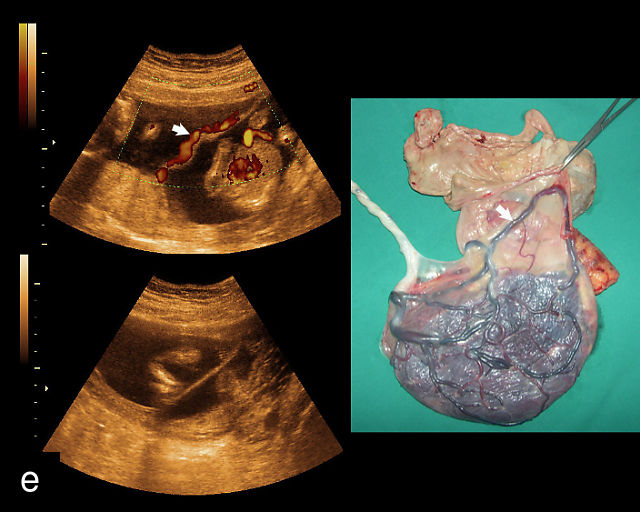

21

(a) Type-1 vasa previa. Photograph after delivery showing the umbilical cord inserting into the membranes through which unprotected fetal vessels run to insert into the placental edge. (b) Type-2 vasa previa. Photograph after delivery showing bilobed placenta with unprotected fetal vessels running though the membranes between the lobes. (c) Type-3 vasa previa in a twin pregnancy. Photograph after delivery showing unprotected vessels running through the membranes from one edge of the placenta to another (arrow). (d) Transabdominal grayscale ultrasound of the lower uterine segment showing a linear hypoechoic structure (fetal vessel) running over the cervix (c) indicating vasa previa (Type 2). b, bladder; h, fetal head. (e) Transabdominal color Doppler ultrasound of the lower uterine segment showing fetal vessels (arrow) running over the cervix (c) indicating vasa previa (Type 2). (f) Transabdominal ultrasound with color flow and pulsed-wave Doppler of the lower uterine segment showing a fetal vessel running over the cervix (c) indicating vasa previa (Type 2). Pulsed-wave Doppler demonstrates an umbilical arterial waveform. (g) Transvaginal grayscale ultrasound with showing a Type-2 vasa previa. There are two placental lobes, an anterior (a) and a posterior (p) lobe. There is a linear and circular hypoechoic structure (arrow) running over the cervix (c) between the lobes. (h) Transvaginal grayscale ultrasound image of vasa previa. A hypoechoic linear structure (arrow) is seen running through the membranes over the cervix (c). h, fetal head. (i) Transvaginal grayscale ultrasound of vasa previa. Hypoechoic circular and linear structures are seen close to the internal os. (j) Transvaginal color Doppler ultrasound image of vasa previa. A fetal vessel is seen running through the membranes over the internal os (arrow) of the cervix (c). h, fetal head. (k) Transvaginal ultrasound with color Doppler showing a Type-2 vasa previa. There are two placental lobes, an anterior and posterior lobe (pl). Fetal vessels run over the cervix between the lobes. (l) Transvaginal color flow ultrasound with pulsed-wave Doppler image of vasa previa. Color Doppler shows flow through the vessel and pulsed-wave Doppler shows a fetal umbilical venous waveform. (m) Transvaginal color ultrasound with pulsed-wave Doppler image of vasa previa. Color flow Doppler shows flow through the vessel and pulsed-wave Doppler shows a fetal umbilical arterial waveform. (n) Transvaginal three-dimensional ultrasound with color Doppler image of vasa previa. h, fetal head; c, cervix.

12

Transvaginal ultrasound imaging of Type-1 vasa previa. Color Doppler (a,c,d) and grayscale (b) imaging shows fetal vessels running over the cervix.

In all pregnancies, the placental cord insertion should be identified at the time of the second-trimester anatomy scan. In addition, a color flow Doppler sweep of the region overlying the cervix should be performed. The ultrasound appearance of vasa previa is of hypoechoic linear or circular structures overlying or in close proximity to the internal os (Figure 21).30,187,252,263 When these are observed, color flow Doppler should be employed to confirm flow through these structures.30,187 Transvaginal ultrasound with color and pulsed-wave Doppler is essential for diagnosing vasa previa; the presence of a fetal arterial or venous waveform on pulsed-wave Doppler confirms the diagnosis (Figure 21). A common misconception is that vasa previa occurs only when a fetal artery overlies the cervix; however, a fetal vein overlying the cervix also constitutes vasa previa (Figure 21l).265 The precise distance of fetal vessels from the internal os required to define vasa previa has been debated.266 While some have used a distance of 2 cm, others argue that unprotected fetal vessels within 5 cm of the internal os are at risk of rupture, particularly given that the cervix dilates to 10 cm during labor. Some experts advocate for a 5-cm threshold to define vasa previa.266,267 An international Delphi consensus of vasa previa experts recommended that the definition should not be limited to a 2 cm cutoff, acknowledging the variability in clinical practice.268

Transvaginal ultrasound with color flow Doppler is highly accurate in the diagnosis of vasa previa, with a systematic review and meta-analysis finding sensitivity and specificity of greater than 99%.269

False positives may arise due to several factors, including funic presentation (where free loops of the cord overlie the cervix), movement artifacts on color Doppler, placenta previa or maternal vessels.30,263 Free loops of the umbilical cord typically move away from the cervix with changes in maternal position and do not persist on serial ultrasound examinations.187

When vasa previa is suspected during the second trimester, transvaginal sonography with color Doppler should be repeated at around 32 weeks to confirm the diagnosis. This follow-up is essential, as 15–40% of vasa previa cases identified in the second trimester resolve spontaneously before delivery.270,271 It is also critical to ensure that the fetal head is not engaged, as this can compress and obscure fetal vessels, potentially leading to a false-negative diagnosis.272 In such cases, manual elevation of the fetal head may be necessary, but care must be taken to avoid compressing the vessels during this maneuver, as it can also result in a missed diagnosis.273